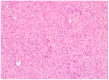

Neurofibromatosis type 1 (NF1) is a common genetic disease whose dermatological lesions are at the forefront of its development. Cutaneous manifestations include café au lait spots, intertriginous freckling, and neurofibromas which appear during childhood and adolescence and are part of the clinical criteria to diagnose NF1. However, it is only recently that oral manifestations have been highlighted in many studies as frequently associated to NF1. This article aims to review oral and cutaneous manifestations related to NF1 and to report a case of a 51-year-old male with skin and oral neurofibromas related to NF1. Our patient presented with lesions on the gingiva, a rare localization that takes a hypertrophic form mimicking other various pathological conditions. Although not frequent, malignant transformation in NF1, especially regarding plexiform neurofibromas, is well established. Patients with NF1 therefore have regular follow-ups based on clinical examination, as sarcomatous transformation brings an extremely poor prognosis, recurrences and distant metastasis being common.